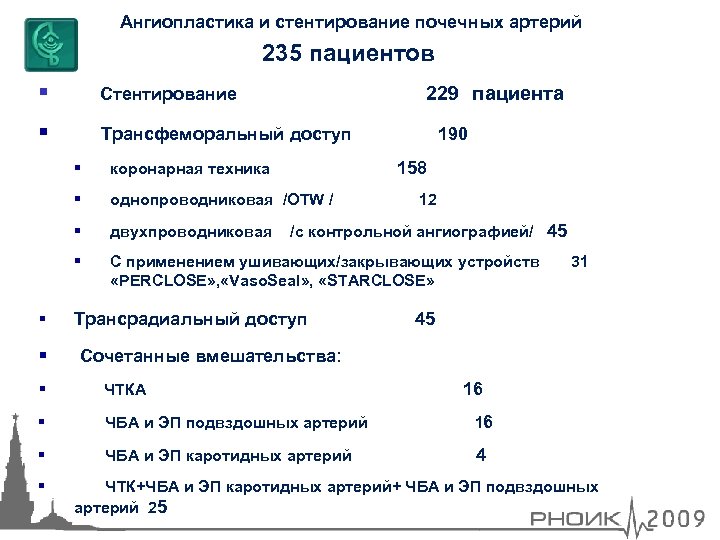

Ангиопластика и стентирование почечных артерий 235 пациентов Стентирование Трансфеморальный доступ 229 пациента 190 158 двухпроводниковая однопроводниковая /OTW / коронарная техника С применением ушивающих/закрывающих устройств «PERCLOSE» , «Vaso. Seal» , «STARCLOSE» 12 /с контрольной ангиографией/ 45 Трансрадиальный доступ 31 45 Сочетанные вмешательства: ЧТКА ЧБА и ЭП подвздошных артерий 16 ЧБА и ЭП каротидных артерий 4 16 ЧТК+ЧБА и ЭП каротидных артерий+ ЧБА и ЭП подвздошных артерий 25

Ангиопластика и стентирование почечных артерий 235 пациентов Стентирование Трансфеморальный доступ 229 пациента 190 158 двухпроводниковая однопроводниковая /OTW / коронарная техника С применением ушивающих/закрывающих устройств «PERCLOSE» , «Vaso. Seal» , «STARCLOSE» 12 /с контрольной ангиографией/ 45 Трансрадиальный доступ 31 45 Сочетанные вмешательства: ЧТКА ЧБА и ЭП подвздошных артерий 16 ЧБА и ЭП каротидных артерий 4 16 ЧТК+ЧБА и ЭП каротидных артерий+ ЧБА и ЭП подвздошных артерий 25